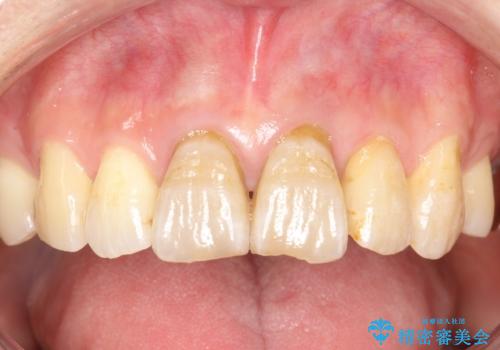

変色した前歯をセラミックできれいに レイヤリングセラミック

前歯のセラミック治療では、他の歯と色調をそろえるのが非常に難しいです。

他の歯に亀裂や白濁など複雑な色合いがある場合、それらをセラミックで再現することも可能ですが、スタンダードのオールセラミックではある程度の同調となります。

かぶせ物の種類: PFZ standard